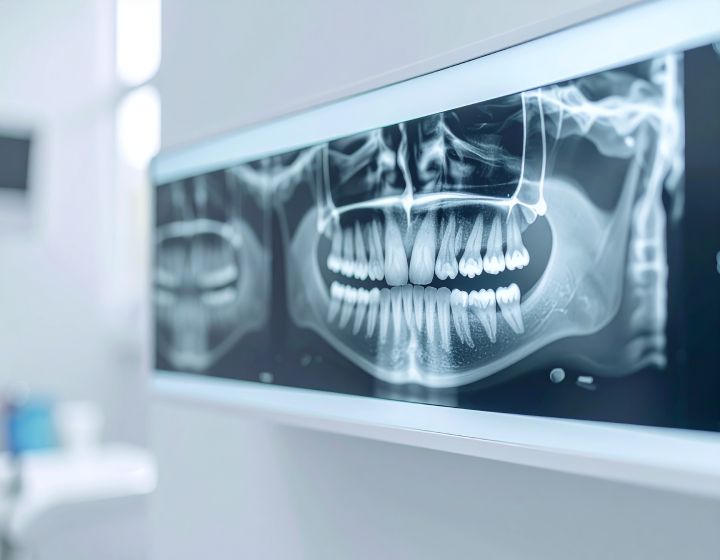

Panoramic X-rays capture your entire dentition and surrounding anatomical structures in one image. These scans are helpful for detecting unusual growths, tumors, or other pathologies that might not appear on traditional X-rays.